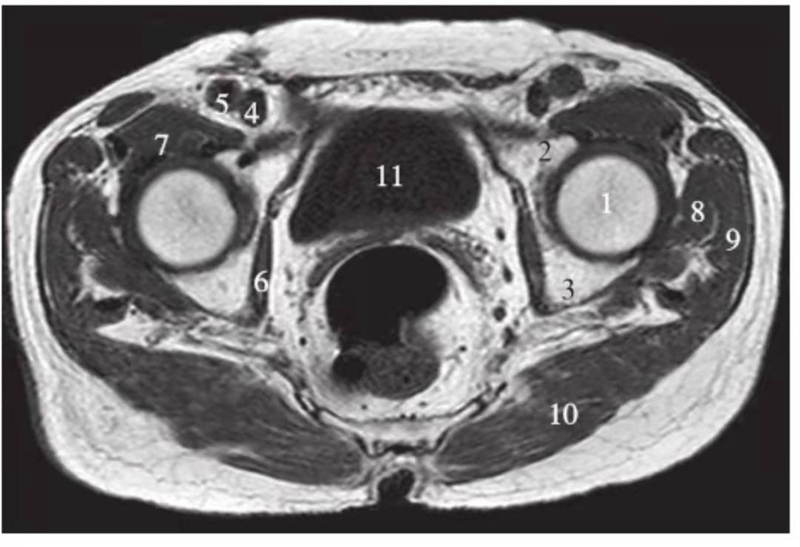

正常髋关节经股骨颈层面T1WI像

1.股骨头;2.股骨颈;3.转子间部;4.髋臼后唇;5.耻骨联合;6.髂腰肌;7.闭孔内肌;8.臀大肌